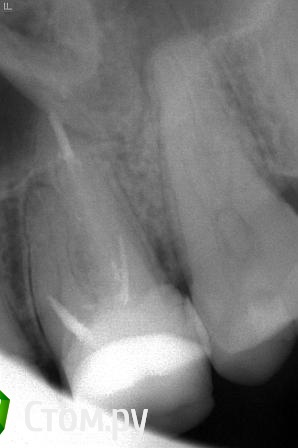

felicidade Опубликовано 30 июня, 2014 Поделиться Опубликовано 30 июня, 2014 Celovek, я не врач, но занимаюсь сейчас тем же, чем и вы: перепломбировкой своих ранее безобразно запломбированных каналов.Покажу вам 2 рентгена: до перепломбировки у эндодонта с микроскопом и, соответственно, после. Мне, как неспециалисту, разница между моим финальным рентгеном и вашим очевидна. Ссылка на комментарий